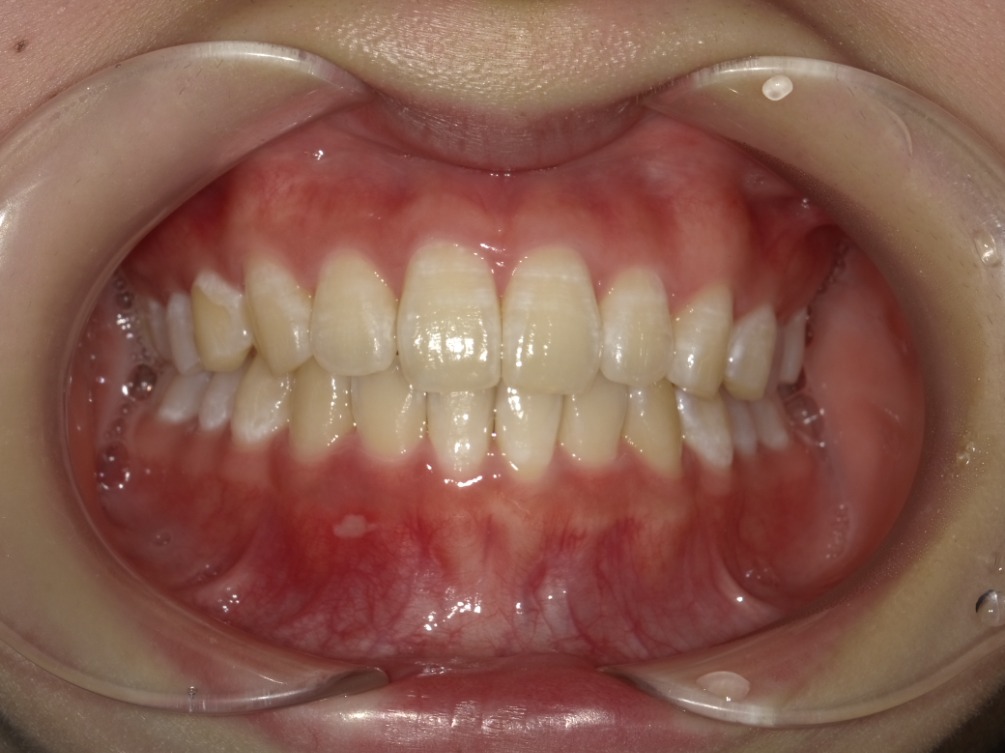

• BEFORE

症例集 インビザライン 正面

矢印

AFTER

正面

治療内容

インビザライン 全顎

治療詳細

叢生や交叉咬合を整えるために、歯の表面にアタッチメント(白い突起)をつけ、IPR(歯と歯の間を削る)を行いました。

患者情報

10代 女性

一期治療から移行

主訴

歯のがたつき

一部分のみかみ合わせが反対

治療期間

2025.3.22~2025.9.27

来院回数:6回

治療費用

検査代 0円

本体代 300,000円 (税込330,000円)

保定代 40,000円 (税込44,000円)

担当医

田中一郎 歯科医師

副作用

マウスピースを1日約20時間装着する必要があるため、しっかりと装着いただけないと歯並びが綺麗になりません